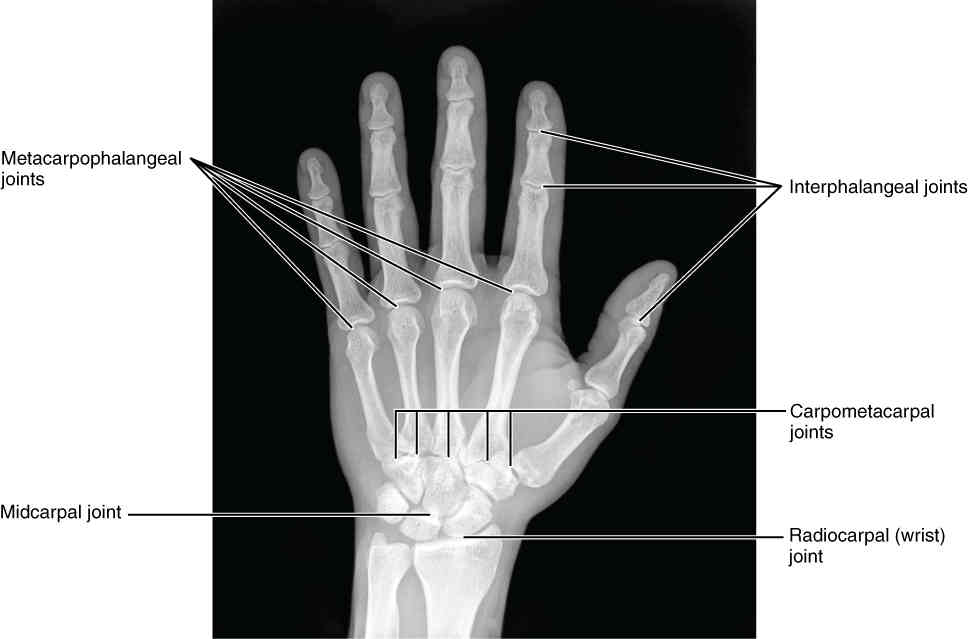

This page is under construction. For now, it is just a resource of the images found in the OpenStax Anatomy and Physiology Handbook. It wil slowly change into a revision tool. Each slide has a number. Use this to refer to the slide. When completed, it will have an unlabelled section, with labelled slides in parallel. On the unlabelled slides, write your answer and use the labelled slide to assess yourself. Keep track by also noting the number on each slide. Improvement at each attempt is important, more so than full marks on a first attempt.